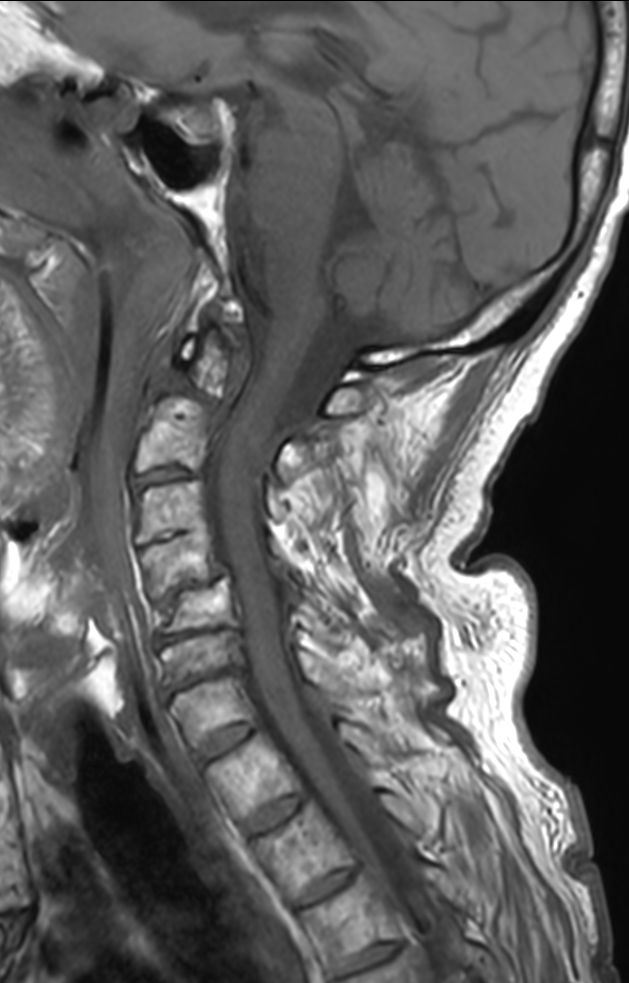

Cervical Spine - Cord lesion

T1w TSE